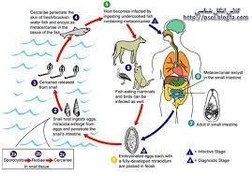

قیمت: 22٬000 تومان - دسته بندی فایل: علوم پزشکیپاورپوینت بیماری هتروفیس

فروش ویژه پاورپوینت حرفه ای بیماری هتروفیس با تخفیف استثنایی فقط 48600 تومان تعداد اسلاید : 12 اسلاید